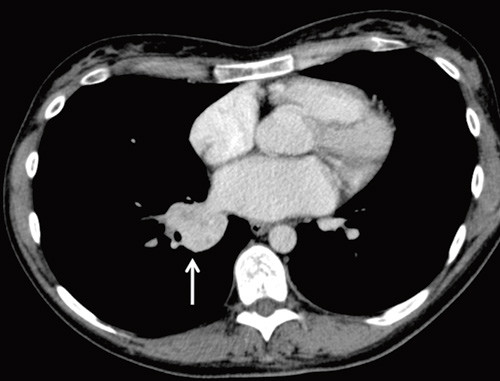

Røntgen thorax tatt omtrent et halvt år etter symptomdebut viste en litt uskarpt avgrenset fortetning i tilknytning til høyre lungehilus. Supplerende computertomografi (CT) av thorax viste en relativt velavgrenset solid fortetning, 3,7 × 3,4 × 3,5 cm, i nedre del av høyre lungehilus (fig 1). Blodprøvene viste nå normal CRP, hvite blodceller og senkningsreaksjon (SR). Pasienten hadde tørrhoste, anstrengelsesrelatert dyspné og vedvarende moderate plager i den grad at hennes fysiske yteevne var redusert. Hun hadde ingen kjent astma eller allergi. På grunn av vedvarende symptomer og røntgenfunn ble hun henvist til snarlig utredning ved lungepoliklinikken.

En lungefortetning kan være et alvorlig funn og krever snarlig avklaring, særlig med tanke på malignitet. Fortetninger i lungehilus kan representere både maligne og benigne tilstander. Av maligne tilstander må man blant annet tenke på primær lungetumor, lymfom og metastaser. Fortetninger kan også ha infeksiøs årsak, for eksempel pneumonisk infiltrat eller abscess. Andre differensialdiagnoser kan være atelektase, granulomer eller benigne tumorer. For nærmere diagnostikk bør det gjøres bronkoskopi med cytologisk og bakteriologisk prøvetaking. Samtidig bør det tas CT- eller ultralydveiledet biopsi, enten transbronkialt eller perkutant.